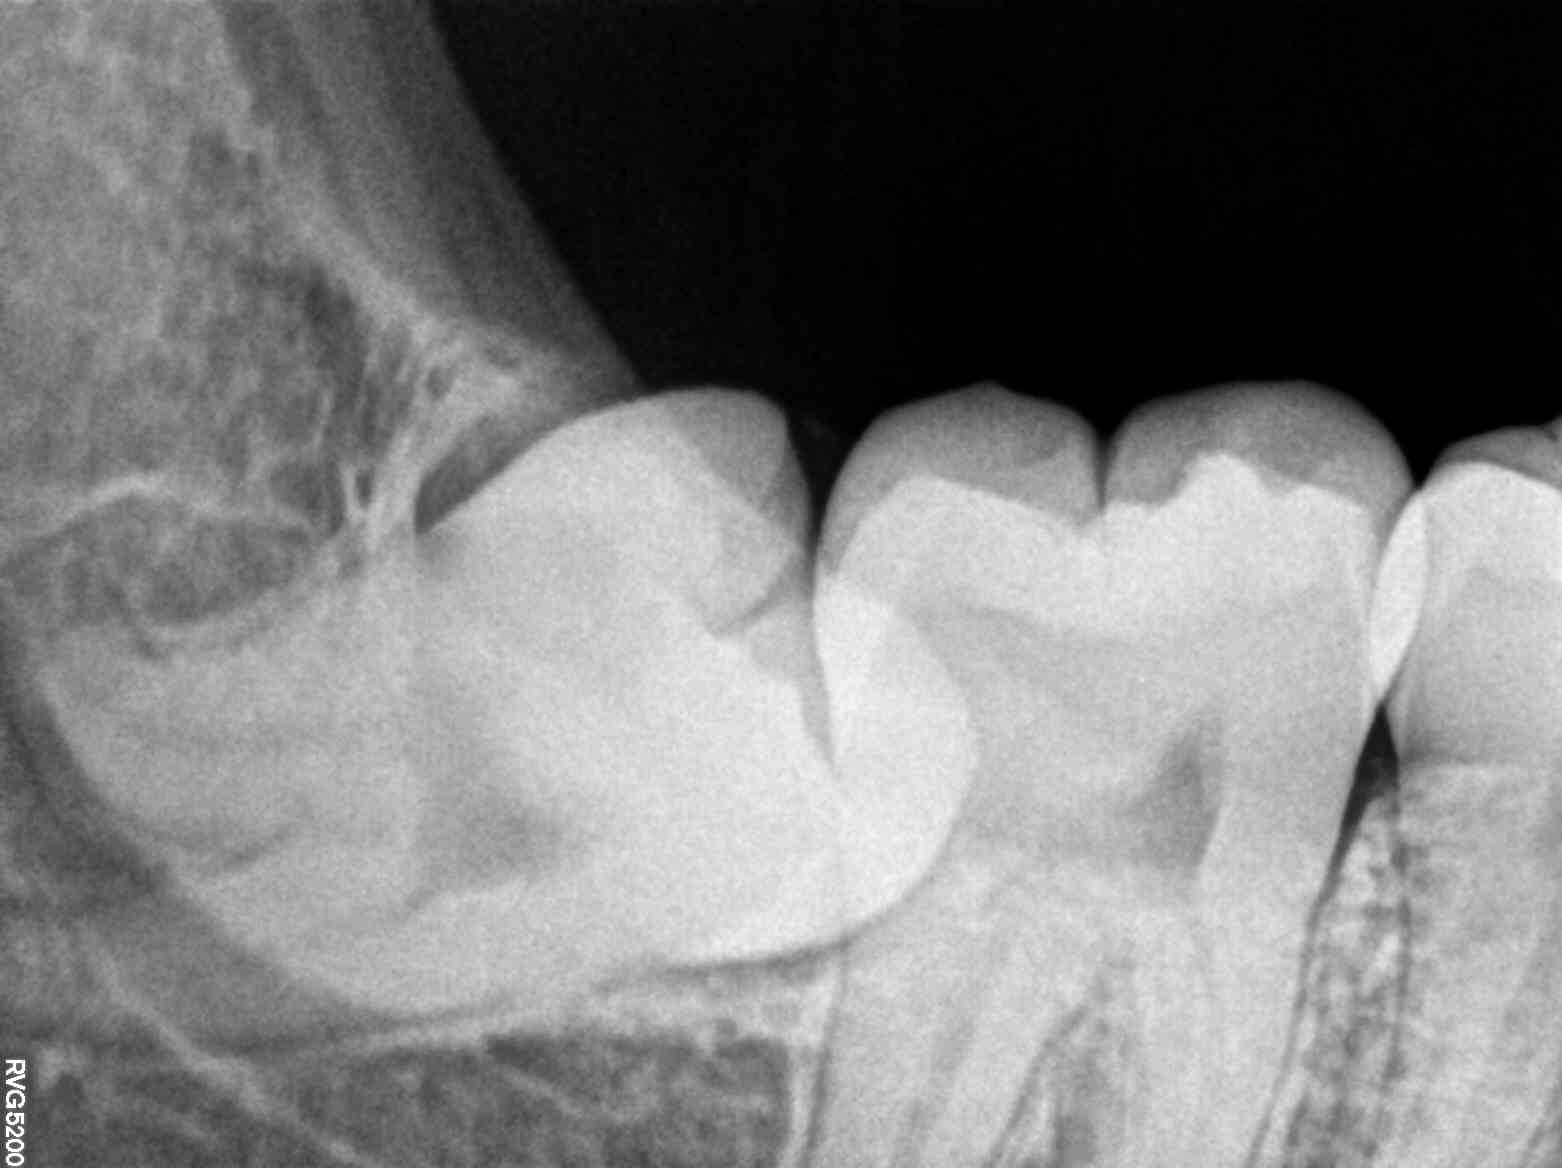

As the X-ray machine quietly captured detailed images, Kavita felt a wave of relief. The entire procedure was over in minutes, devoid of the uncomfortable moments she had come to dread. What she found most reassuring was the immediate feedback. Dr. Mehta walked her through the high-resolution images displayed on a screen, pointing out areas that required attention and those that were perfectly healthy.

This transparency and the ability to visualize her dental health in real-time transformed Kavita’s perception of dental care. She realized that the fear of the unknown, which had plagued her for years, was dissipating. With the aid of modern X-ray technology, she felt empowered and informed, ready to take proactive steps toward maintaining her oral health.